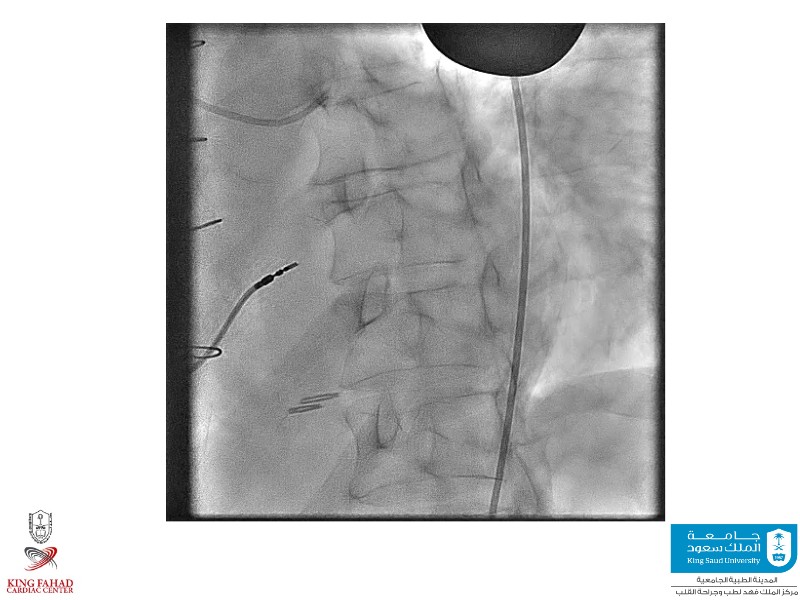

This session helps you anticipate and address complex scenarios such as mitral valve-in-valve, TAV-in-SAV, and valve-in-valve-in-valve procedures. Learn from expert case discussions that explore procedural strategies, technical challenges, and best practices to optimize outcomes in redo structural heart interventions.